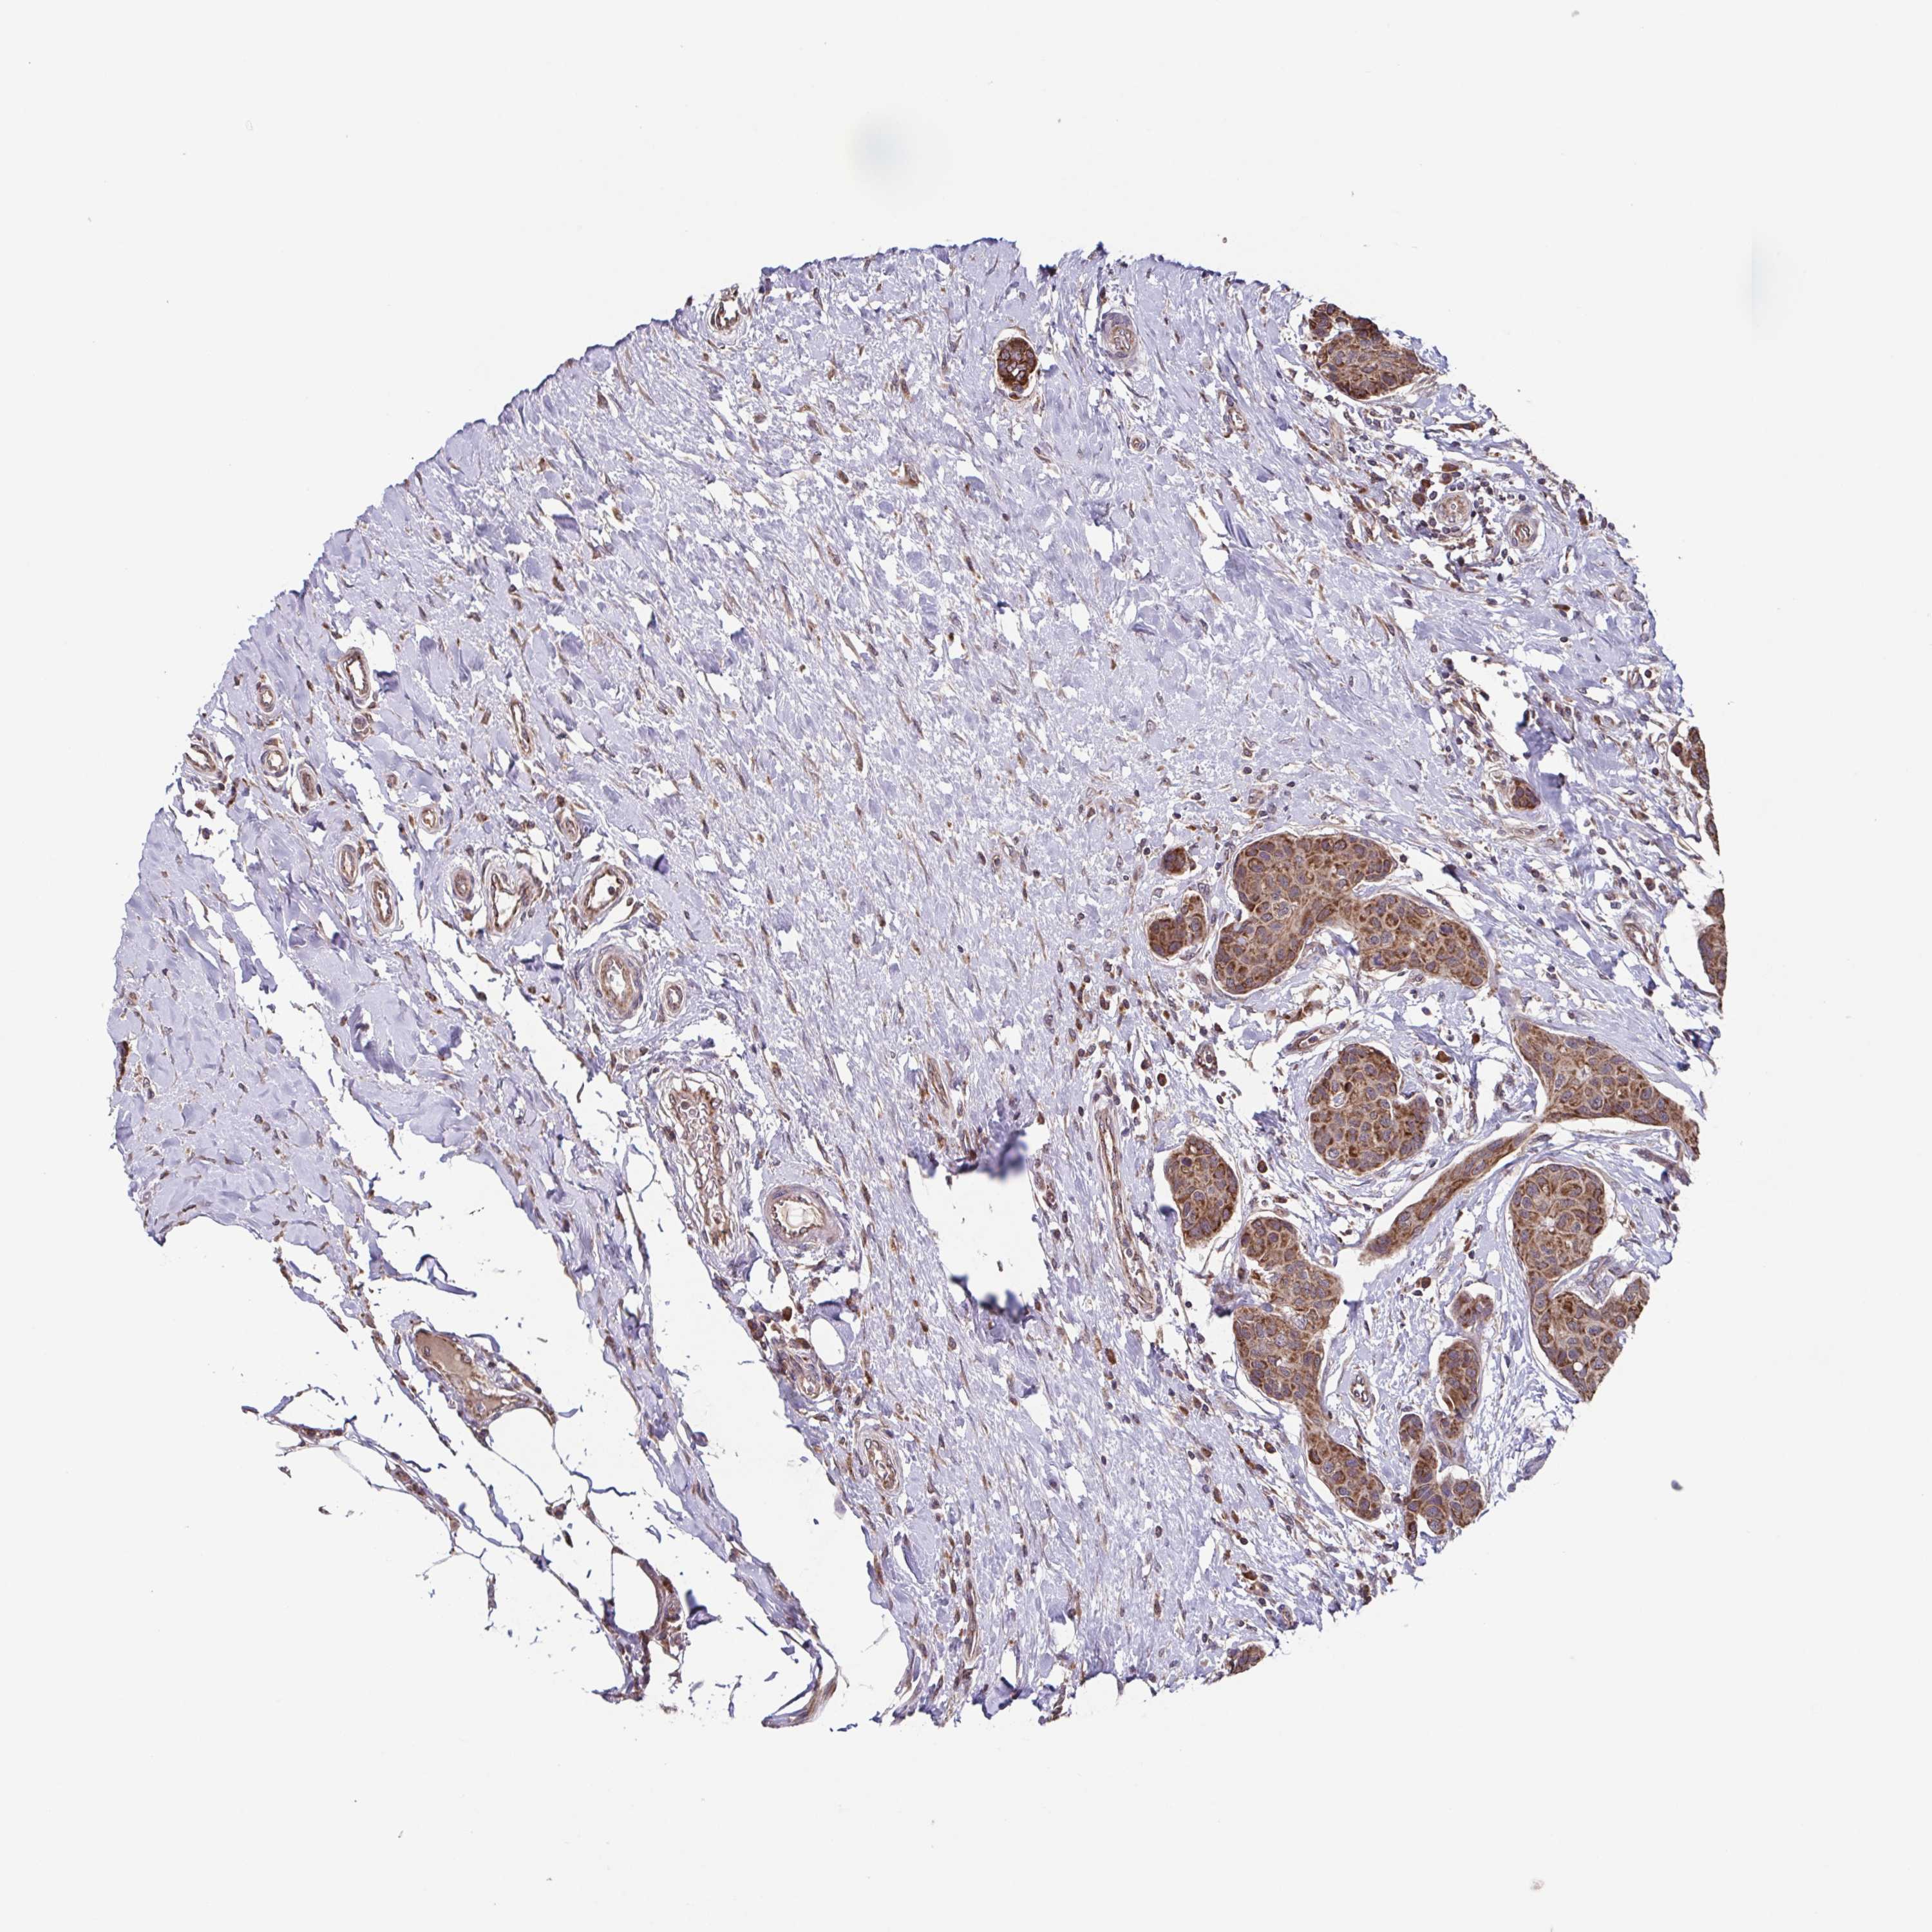

CANCER BREAST CANCER Show tissue menu

BRCA TCGA BRCA VALIDATION PROTEIN EXPRESSION

ANTIBODIES

AND

VALIDATION